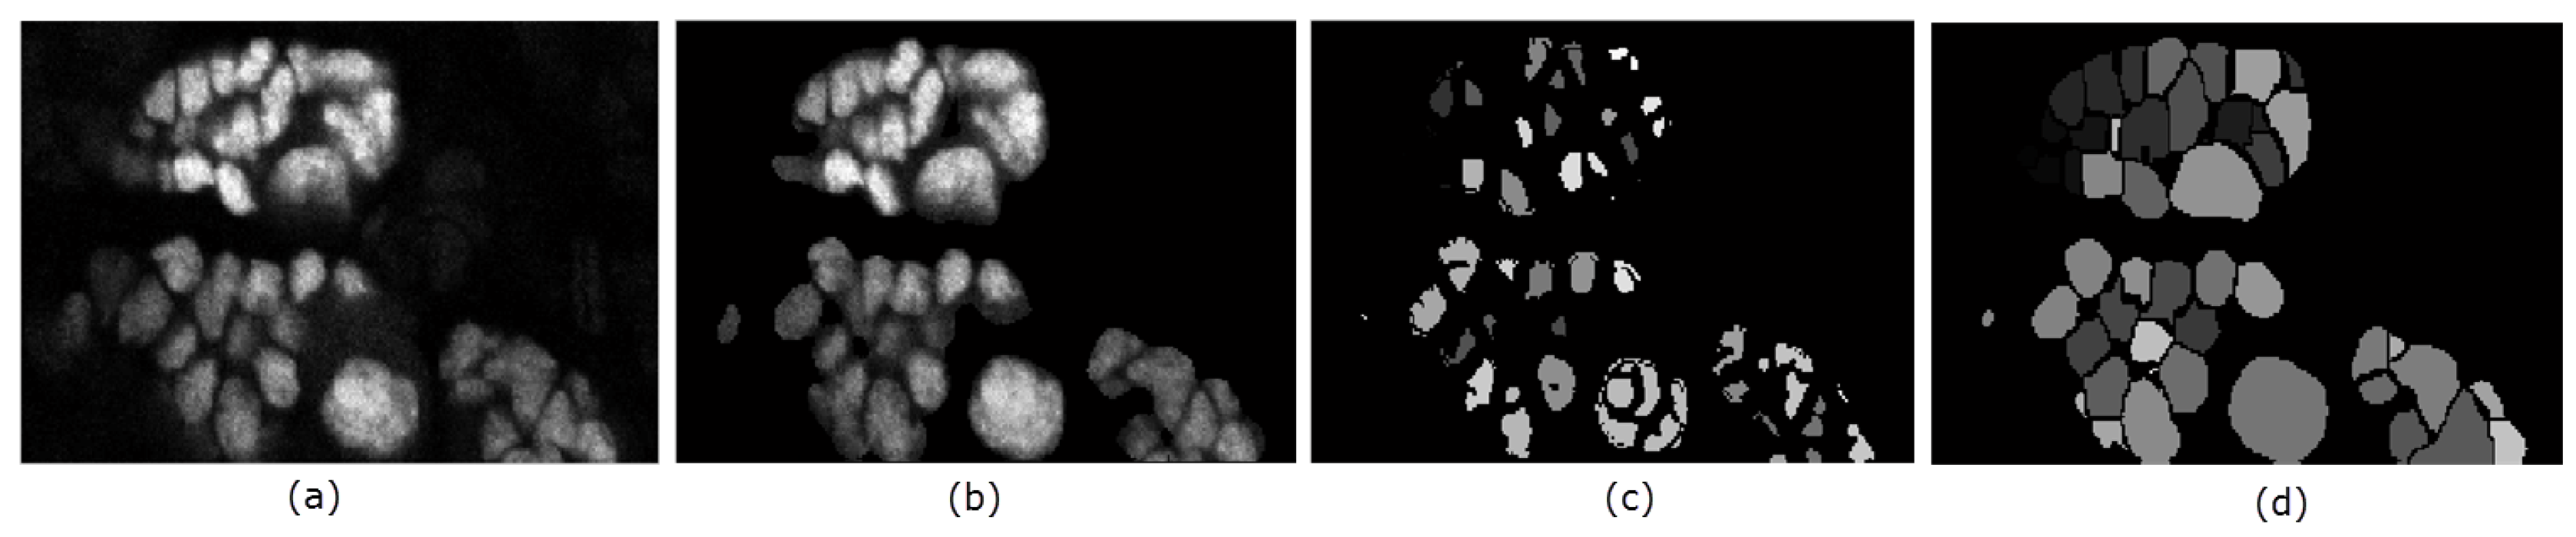

4.3. Data Pre-processing

4.4. Seed Detection and Watershed